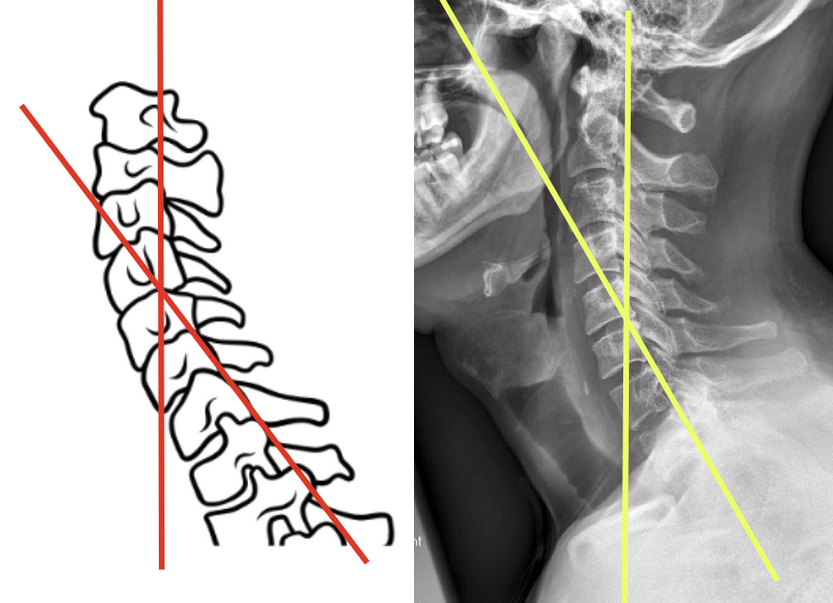

Method 1 (endplates/ Cobb Method)

Use a neutral lateral cervical spine X-ray.

Identify the inferior endplate of C2 and the inferior endplate of C7.

Draw a line along each endplate.

Then, draw perpendicular lines from both of these endplate lines.

Measure the angle formed at the intersection of the two perpendiculars.

This angle is the C2–C7 Cobb angle, representing cervical lordosis.

Method 2 (posterior tangent method/ Harrison method)

On a neutral lateral cervical X-ray, draw a line along the posterior border of the vertebral body of C2.

Draw a second line along the posterior border of the vertebral body of C7.

Extend these lines until they intersect.

The angle between them is recorded as the posterior tangent angle, which represents cervical lordosis.

This method is called the "posterior tangent method" or Harrison method. Some studies suggest it may be more sensitive to subtle curvature changes, especially in the mid-cervical region. It may yield slightly different values than the Cobb method—so always document which technique you're using for consistency and comparison.

Cobb Method

Posterior Tangent/Harrison Method